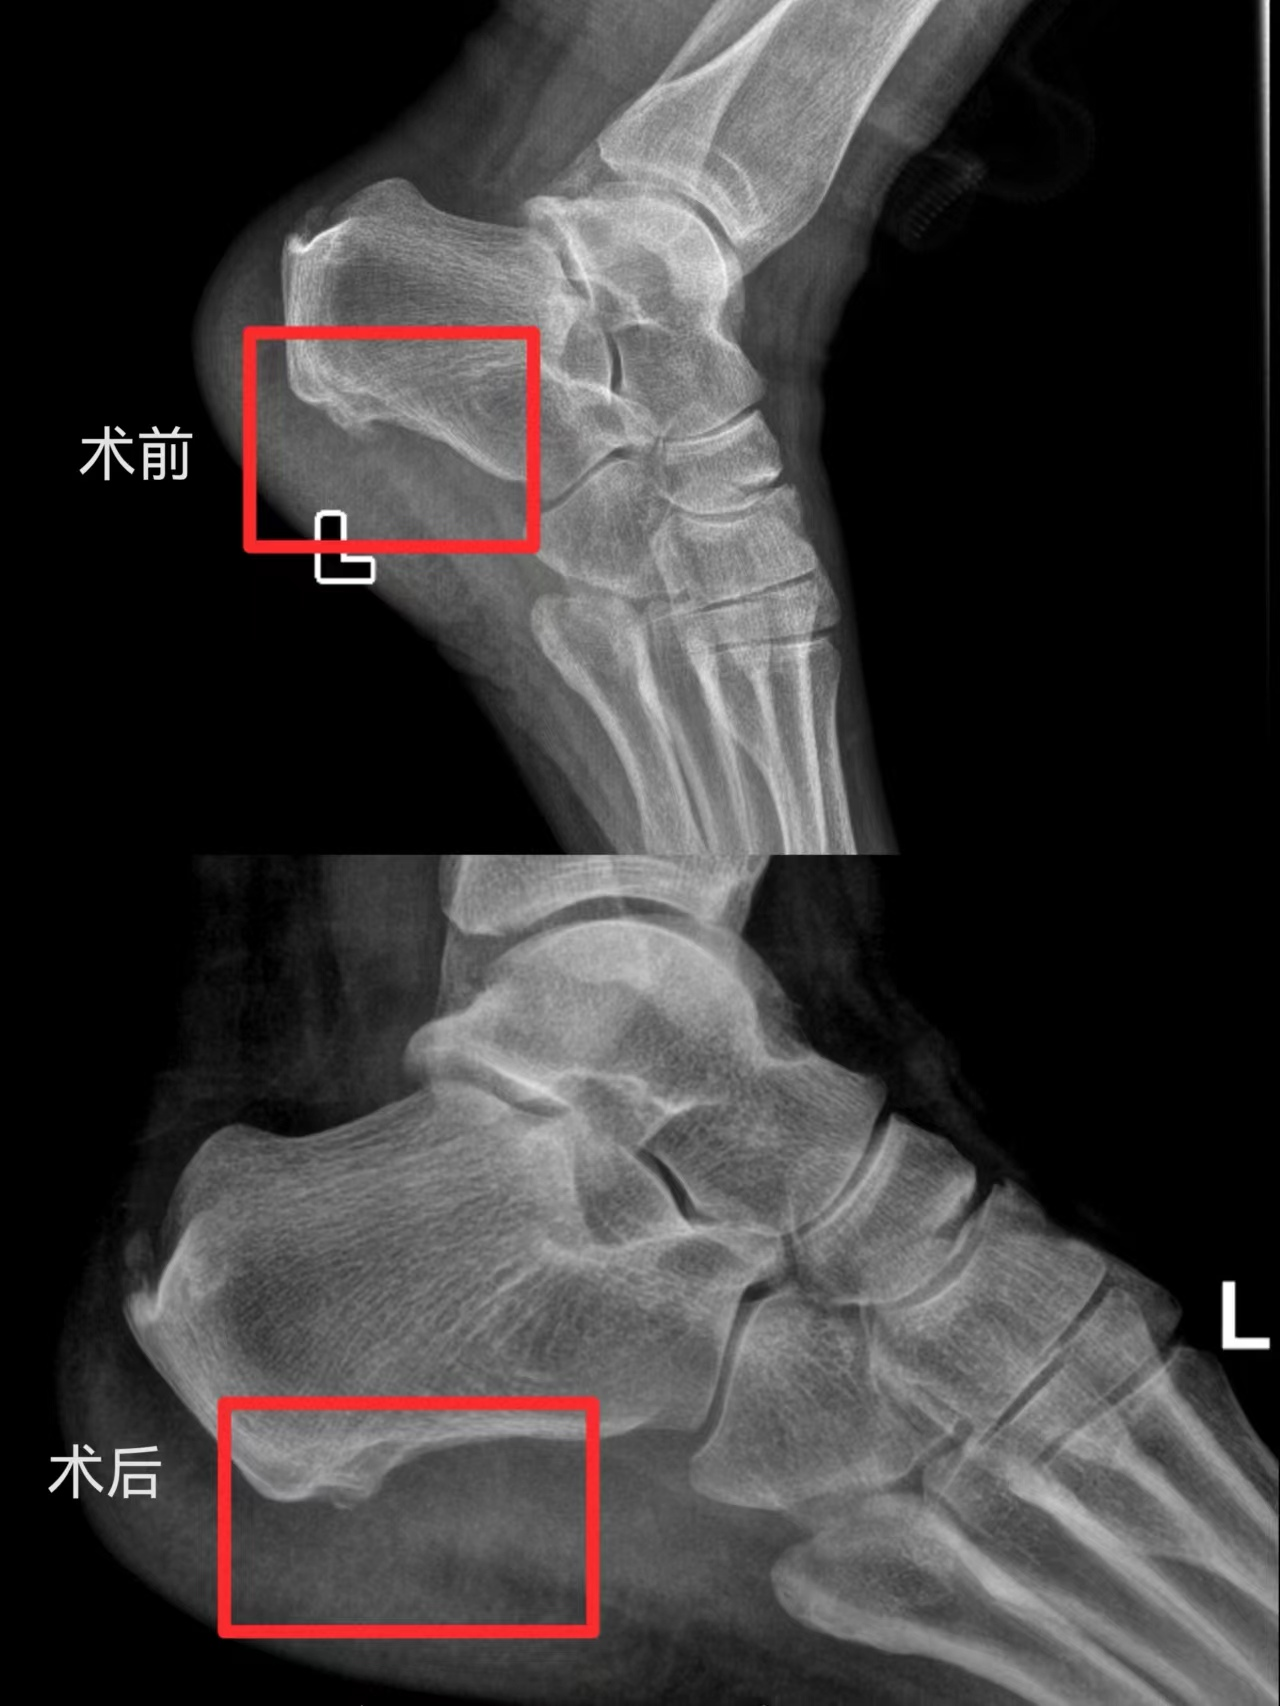

患者何某,4月份出现行走后左足跟部反复疼痛,休息后缓解,近期愈发加重,此前患者曾在当地卫生院尝试理疗、局部封闭等各种治疗方法效果均不理想,遂入我院骨外Ⅲ科治疗。科室接诊后,查体发现患者左侧足底后跟部压痛明显,经筛查排除了痛风、类风湿关节炎、骨折、骨髓炎等相关疾病。X线片可见左侧跟骨骨质增生、有骨刺形成,综合分析确诊为左侧跟骨骨刺并足底跖筋膜炎。

科主任邓军荣组织团队医生进行认真充分的术前讨论后,决定为患者行关节镜下行左跟骨病损切除术+左跖筋膜松解术。由周全医生主刀:手术取足跟部内侧两个长约0.5cm小切口,术中利用关节镜直达病灶,直视下切除跟骨骨刺,松解跟骨结节附着的跖筋膜,切除骨刺与跖筋膜之间的慢性炎性组织,避免了骨刺复发的可能。手术顺利完成,术后第二天患者便可下地行走,并在医生及护士详细告知相关注意事项后办理出院。